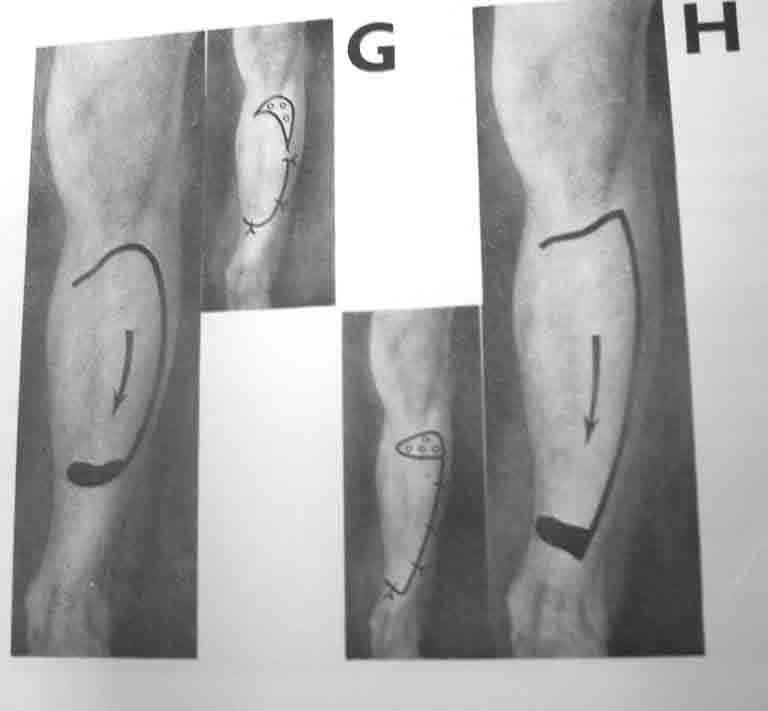

Глубокоуважаемый Павел Анатольевич! БОльшое спасибо за исчерпывающие комментарии! С Капланом, согласен, погорячился. Как Вы считаете, возможна ли в этой ситуации пластика перемещенным кожным лоскутом на широком основании (например, как на прилагаемом фото)?

Данный лоскут не имеет осевого кровоснабжения. Операция по его выделению травматичная. У пациента 60 лет очень высокий риск некроза этого лоскута после его отслойки. А если даже 50% площади этого лоскута некротизируется, то мы получим рану, во много раз большую, чем исходная. Я бы не стал его использовать.

При отсутствии альтернативы закрытия дефекта специалистом, тогда кожным лоскутом на широком основании "cross leg flap". Рекомендую подготовку донорского участока заранее, на задней поверхности голени, срез кожи с подкожной клетчаткой, как на вашем рисунке, приподнимается лоскут от фасции, после гемостаза кожа зашивается заново.

Таким образом подготовленный участок хорошо приживается засчет образования краевого кровообращения, особенно у пожилых и у больных с заболеваниями периферических сосудов. Через 10-12 дней лоскут повторно выделяется по заживающей линии и закрывается дефект, а на донорский участок кожная пластика.